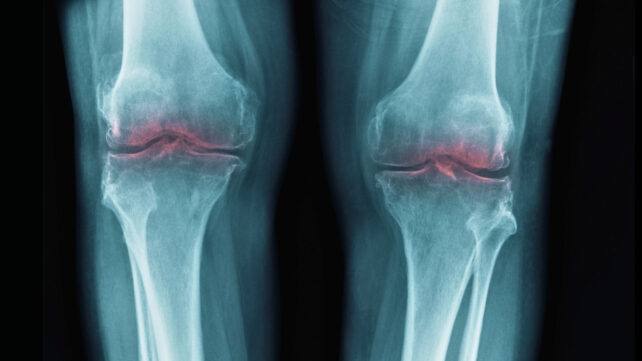

That led scientists to consider whether 15-PGDH might be involved in osteoarthritis, where stress on joints leads to the breakdown of collagen in cartilage, causing inflammation and pain.

In tests on old mice, knee cartilage that had previously worn down thickened following the introduction of a 15-PGDH inhibitor. In similar tests on young, injured mice, the inhibitor offered protection against the usual effects of injury-induced osteoarthritis.

The same experiment was also tried on human tissue samples taken from people having knee replacement surgery. Again, there were clear signs of regeneration, with the cartilage getting stiffer and showing fewer signs of inflammation.